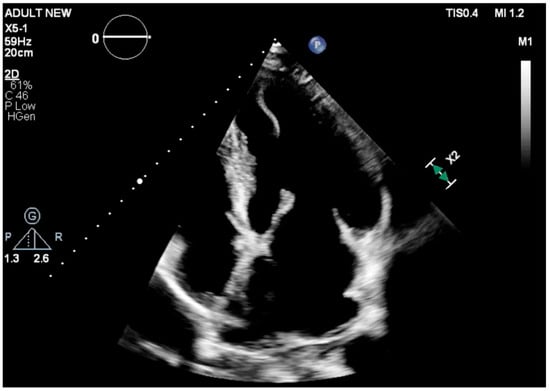

When the Apex Deceives: A Mobile Left Ventricular Mass After Myocardial Infarction

Background and Clinical Significance: Mechanical complications and intracavitary thrombus are both recognized causes of clinical deterioration following acute myocardial infarction, yet they require fundamentally different therapeutic approaches. Distinguishing between these entities is critical, as misdiagnosis may lead to unnecessary surgical intervention or delayed [...] Read more.

Background and Clinical Significance: Mechanical complications and intracavitary thrombus are both recognized causes of clinical deterioration following acute myocardial infarction, yet they require fundamentally different therapeutic approaches. Distinguishing between these entities is critical, as misdiagnosis may lead to unnecessary surgical intervention or delayed anticoagulation with serious consequences. Left ventricular (LV) thrombus typically appears as a well-defined mass; however, atypical and highly mobile morphologies may closely mimic catastrophic post-infarction mechanical complications, creating significant diagnostic uncertainty. This case highlights the pivotal role of contrast-enhanced echocardiography in resolving such ambiguity and guiding appropriate management in a high-stakes clinical setting. Case Presentation: A 60-year-old man presented with acute dyspnea and pulmonary edema ten days after an anterior myocardial infarction treated with percutaneous coronary intervention, complicated by ischemic stroke. Transthoracic echocardiography demonstrated severe LV systolic dysfunction with moderate-to-severe mitral regurgitation and an unexpected, highly mobile, irregular mass protruding into the LV apex. The mass exhibited a shredded, tissue-like appearance, raising urgent concern for post-infarction mechanical complications, including papillary muscle rupture or apical myocardial disruption, and prompting immediate consideration of surgical intervention. Contrast-enhanced echocardiography was performed and revealed a mobile LV apical thrombus. Surgical management was avoided, and systemic anticoagulation was initiated, followed by transition to rivaroxaban in combination with ongoing dual antiplatelet therapy. The patient demonstrated rapid clinical improvement with optimized heart failure treatment and was discharged after four days, with planned follow-up imaging to assess thrombus resolution. Conclusions: Left ventricular thrombus may present with atypical, misleading morphologies that closely resemble life-threatening mechanical complications after myocardial infarction. Full article

Figure 1